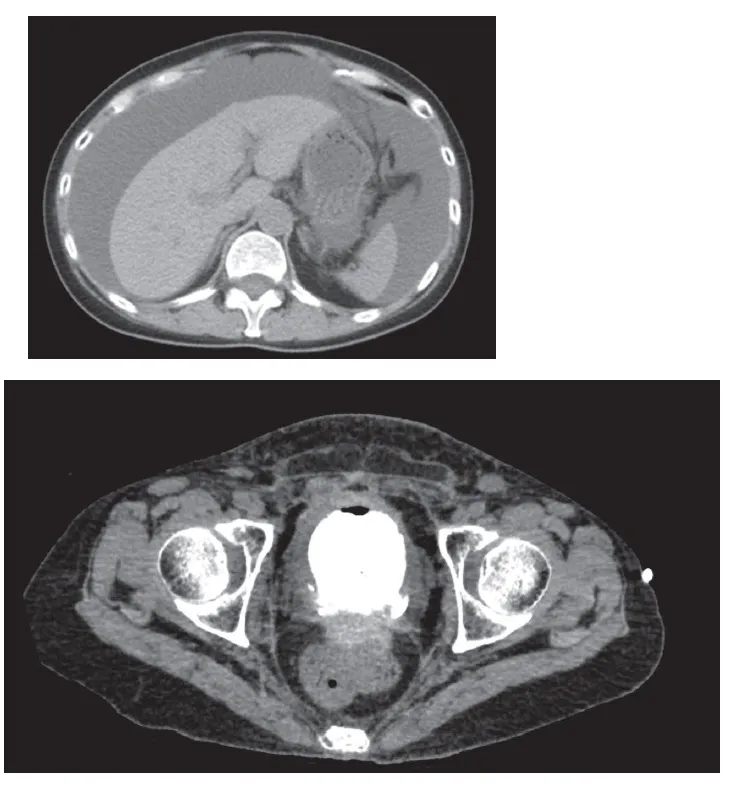

Foi realizada uma tomografia computadorizada do abdômen, sendo identificado uma área de perfuração na parede

posterior-esquerda da bexiga, sugerindo uma ruptura da bexiga. A paciente foi diagnosticada uma perfuração vesical, com fuga de urina para a cavidade peritoneal (figura 2).

Figura 2. TC abdômen mostrando as ascite e vazamento de contraste na bexiga (lado esquerdo da parede posterior da bexiga).